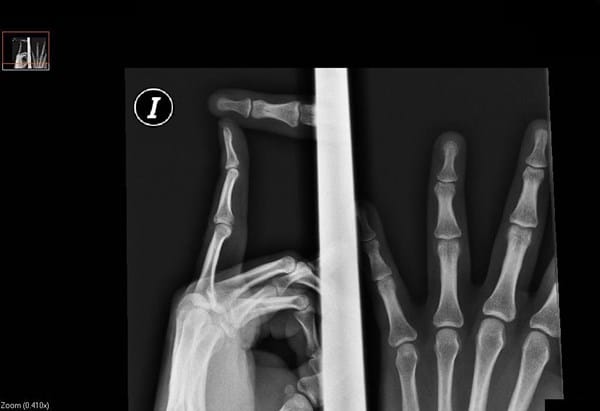

Desde que yo recuerdo (tengo 32 años) la ultima falange del dedo anular de la mano izquierda siempre lo he tenido torcido. Yo creía que había sido un golpe de pequeño contra una puerta. Soy profesor de guitarra y a veces noto bastante molestia. Fui a un fisioterapeuta osteopato y como yo le explique eso, me hizo un tratamiento con acupuntura y aplicación diaria de calor para deshacer una calcificación que en teoría seria lo que tendría. Después de unos meses vimos que no mejoraba nada el dedo. Fui a hacerme una radiografía y me gustaría que alguien me proporcionara otra opinión profesional.